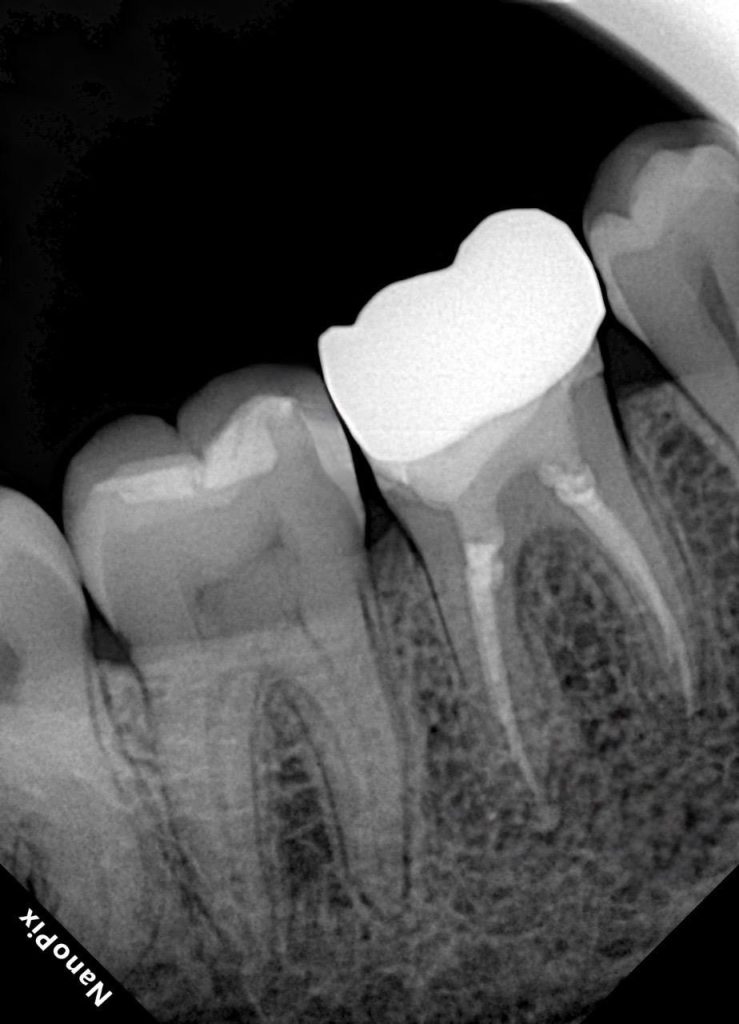

- Radiograph: Excellent apical seal and dense obturation with uniform cement line.

6️⃣ Post-operative radiographs confirming obturation and marginal integrity